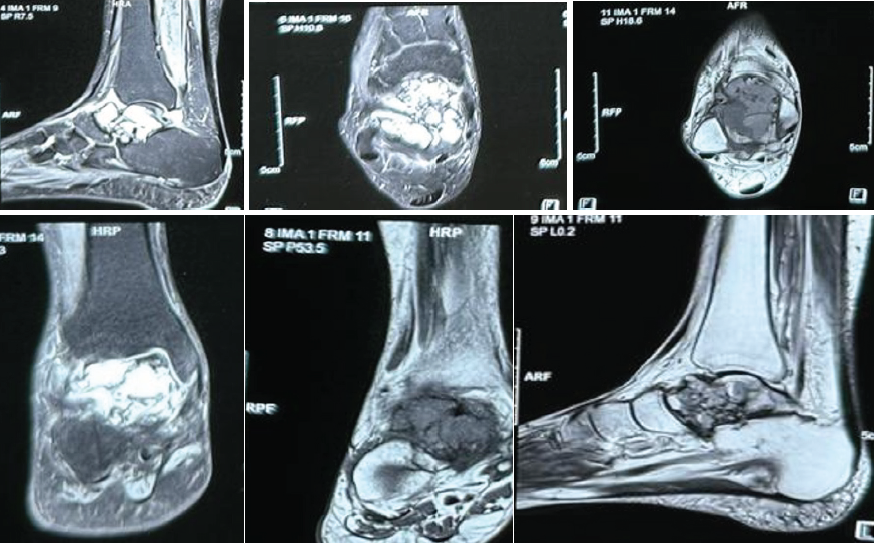

A 32-year-old female presented with complaints of pain and swelling in the dorsum of her foot. The swelling was insidious in onset and was noticed by the patient while bathing and was the size of a pea. It was associated with pain, which was insidious in onset, dull aching in nature, mild to moderate in intensity, with no aggravating or relieving factors, not radiating to any other site, and not relieved by rest. There was no history of trauma as well. Clinical examination revealed the swelling to be hard, attached to the underlying structure, not attached to the overlying skin, non-mobile, non-tender and with no erythema or local rise of temperature. There was no appreciable change in size since the patient had first noticed the swelling. X-rays and magnetic resonance imaging (MRI) were advised to the patient for the same and conservative management was advised (Fig. 1, 2).

Figure 2: Magnetic resonance imaging of the right foot showing large irregular multiloculated expansile cystic lesion measuring approximately 4.1 × 3.1 × 2.2 cm, involving the talar dome and neck reaching up to the anterior articular surface. The lesion appears as heterogeneously hyperintense on T2/short tau inversion recovery images and iso to hypointense on T1-weighted image with multiple intrinsic thick enhancing septae causing loculation with multiple intrinsic blood-fluid level.

X-Rays of the foot of the patient showed a lytic lesion of the right talus bone. A contrast-enhanced MRI was also advised, which showed a large irregular multiloculated expansile cystic lesion, measuring approximately 4.1 × 3.1 × 2.2 cm, involving the talar dome and neck reaching up to the anterior articular surface. The lesion appeared as heterogeneously hyperintense on T2/Short tau inversion recovery images and iso to hypointense on T1-weighted images with multiple intrinsic thick enhancing septae causing loculation with multiple intrinsic blood-fluid levels, suggestive of ABC, and histopathological and clinical correlation was advised. Upon follow-up, image-guided fine needle aspiration cytology (FNAC) and biopsy of the patient were done. The FNAC was suggestive of few scattered multinucleated giant cells along with few degenerated cells against hemorrhagic background, likely a benign lesion (Fig. 3). The biopsy result reported fragmented bone tissue with hemorrhagic cystic spaces lined by osteoclastic giant cells and mononuclear cells with mild anisonucleosis with two possible differentials: Giant cell tumor and ABC, both being quite rare in the talus.